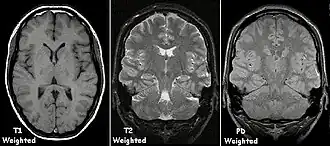

In general, two aspects of the relaxation process are measured: the time taken for the magnetic vector to return to its resting state (also known as T1 or spin–lattice relaxation), and the time taken for the axial spin of the hydrogen protons to return to its resting state (also known as T2 or spin–spin relaxation).[47] To create a T1-weighted image, the MR signal is measured by changing the amount of time between RF pulses (also known as the time to repeat, or TR). To create a T2-weighted image, the MR signal is measured by changing the amount of time between delivering the RF pulse and receiving the RF energy signals from the hydrogen protons (also known as the time to echo, or TE). The dominant signal intensities of T1 image weighting are fluid (black due to low intensity), muscle (grey due to intermediate signal intensity), and fat (white due to high signal intensity). Fat suppression is applied to many T1 weighted sequences to suppress the brightness of the signal created by it. The dominant signal intensities of T2 image weighting are fluid (white), muscle (grey), and fat (white). T2 signals are also often emphasized or suppressed depending on what the goal of the imaging is; notable examples include fat suppression, fluid attenuation, and susceptibility weighting.

Also of note are proton density (PD) weighted images, which are generated using a long TR and a short TE. PD is useful for differentiating between fluid, hyaline cartilage and fibrocartilage, which makes it ideal for imaging joints. Outside of joint imaging it has largely been replaced by fluid attenuated inversion recovery (FLAIR), an inversion recovery sequence that removes the signal from cerebrospinal fluid.[48]